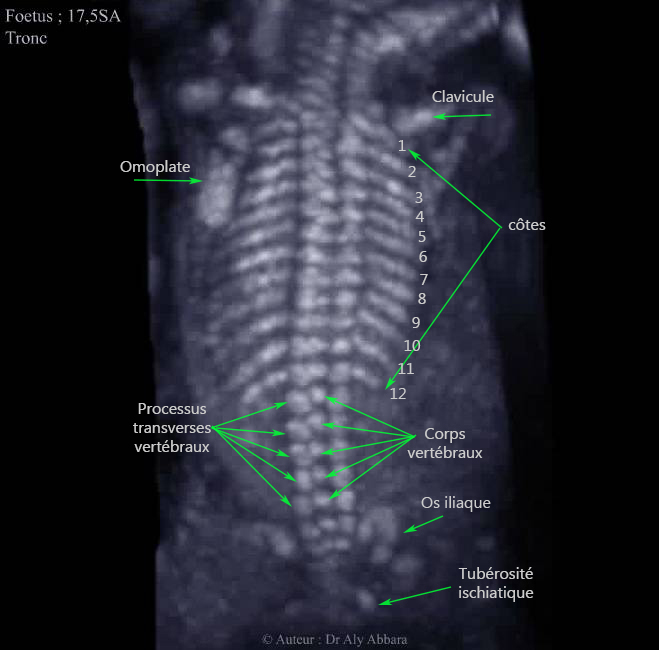

Images échographiques en 3D (os) animées montrant les éléments osseux squelettiques du tronc identifiables par échographie chez un fœtus âgé de 17 SA et 4 jours.

Auteur Dr Aly ABBARA